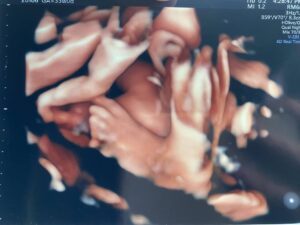

足が大きい赤ちゃん?

お腹にいた時はいたって普通の大きさだったという息子さん。ところが、足だけが大きかったのだそう。

先生に「足が大きいんじゃない!?」と言われたママさんでしたが、1人目の子どもということもあり、よく分からないまま「そんなことある!?」と思ったといいます。

実際にエコーで測ってみると、33週で推定7cm〜8cmの大きさだったのだとか。先生の予想は正しかったようで、2歳現在の息子さんは、17cmのスニーカーを履いています。ちなみにこちらのサイズ、靴屋さんで測ってもらったものだそう。